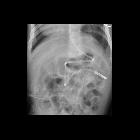

Preschooler

after feeding tube placement. AXR AP shows a feeding tube that appears to loop back upon itself within the stomach before it exits through the pylorus and courses through the duodenum with its tip in the proximal jejunum.The diagnosis was normal position of the tip of the feeding tube in the proximal jejunum.